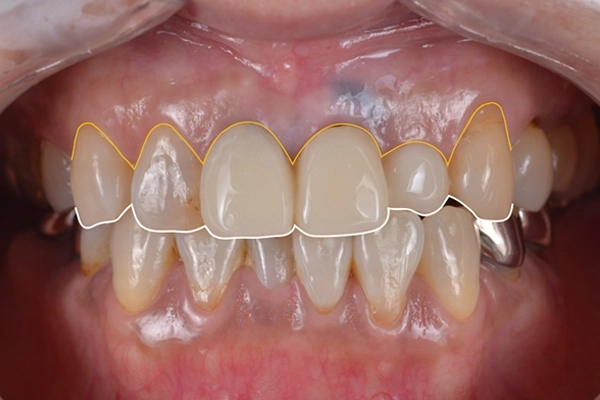

見た目の状態

歯茎のラインと歯の先端のラインが左上2番の影響で不揃いになっていました。

矯正治療の様子

治療前の正面から見た様子です。

矯正後、歯の先端のラインを整えることができました。